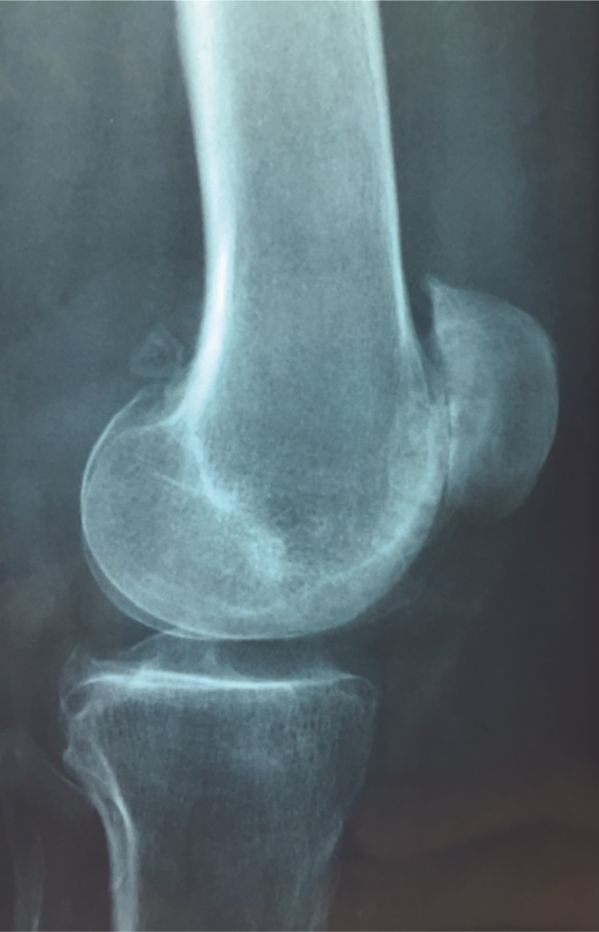

Mise au point Le positionnement des pièces prothétiques dans la prothèse fémoro-patellaire : Les 10 commandements , Franck Remy Clinique de Saint-Omer, 71 Rue Ambroise Paré, 62575 Blendecques, France N°302 - Mars 2021 ● 13 min de lecture

Technique Pourquoi utiliser une voie d’abord latérale dans la prothèse fémoro-patellaire ? , Franck Remy Clinique de Saint-Omer, 71 Rue Ambroise Paré, 62575 Blendecques, France N°302 - Mars 2021 ● 7 min de lecture